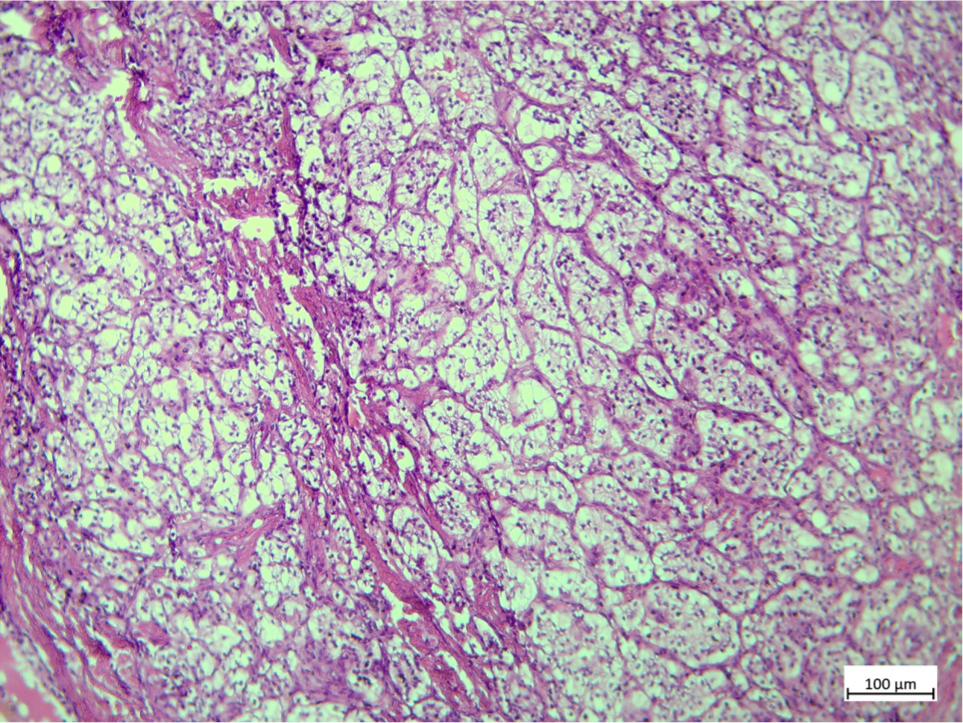

Laboratory tests, including hormonal examination, tumor markers, and semen analysis, were performed. Luteinizing hormone (LH) and follicle-stimulating hormone (FSH) were increased and serum level of testosterone was significantly low. Tumor markers, including lactate dehydrogenase (LDH), alpha-fetoprotein (AFP), and Beta human chorionic gonadotropin (B HCG) were within normal range. Semen analysis revealed azoospermia.Abdominal ultrasonography revealed no abnormal finding. Scrotal sonography demonstrated vascular and heteroechogen masses measuring 19×14 in lower pole of the right testicle, 19×16 mm in upper pole of the right testicle, and 23×16.5 mm in upper pole of the left testicle. After having patient’s informed consent, bilateral orchiectomy was performed by inguinal incision. Histopathologic examination and immunohistochemistry staining revealed metastasis from RCC (Figure 1). Patient was referred for systemic therapy with sunitinib malate (Sutent).

Figure 1: Histopathological examination and immunohistochemistry staining revealed bilateral testicular metastases from renal clear cell carcinoma.